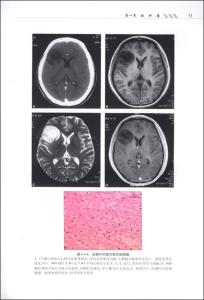

感谢兰州大学第二医院病理科李晓鸣主任提供课件及视频,给大家学习神经病理的机会!